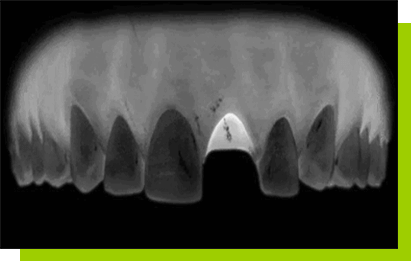

Zawsze wykonujemy trójwymiarowe zdjęcie CBCT. W przypadku jakichkolwiek wątpliwości lekarz stomatolog może zlecić ogólną morfologię krwi lub konsultację z lekarzem rodzinnym. Wtedy wspólnie wydają decyzje o kwalifikacji Pacjenta do zabiegu.

Leczenie, mające na celu wstawienie zębów, planujemy na podstawie dokładnego badania klinicznego w tym badania zgryzu i CBCT. Aby praca była wykonana jak najlepiej pod względem estetycznym i czynnościowym, warto jest przygotować specjalny szablon do dokładnego wprowadzenia implantu. Na tym etapie oprócz przedstawienia Pacjentowi najczęściej dwóch lub trzech alternatywnych metod uzupełnienia implantologicznego, tworzymy również wstępny kosztorys całego leczenia.